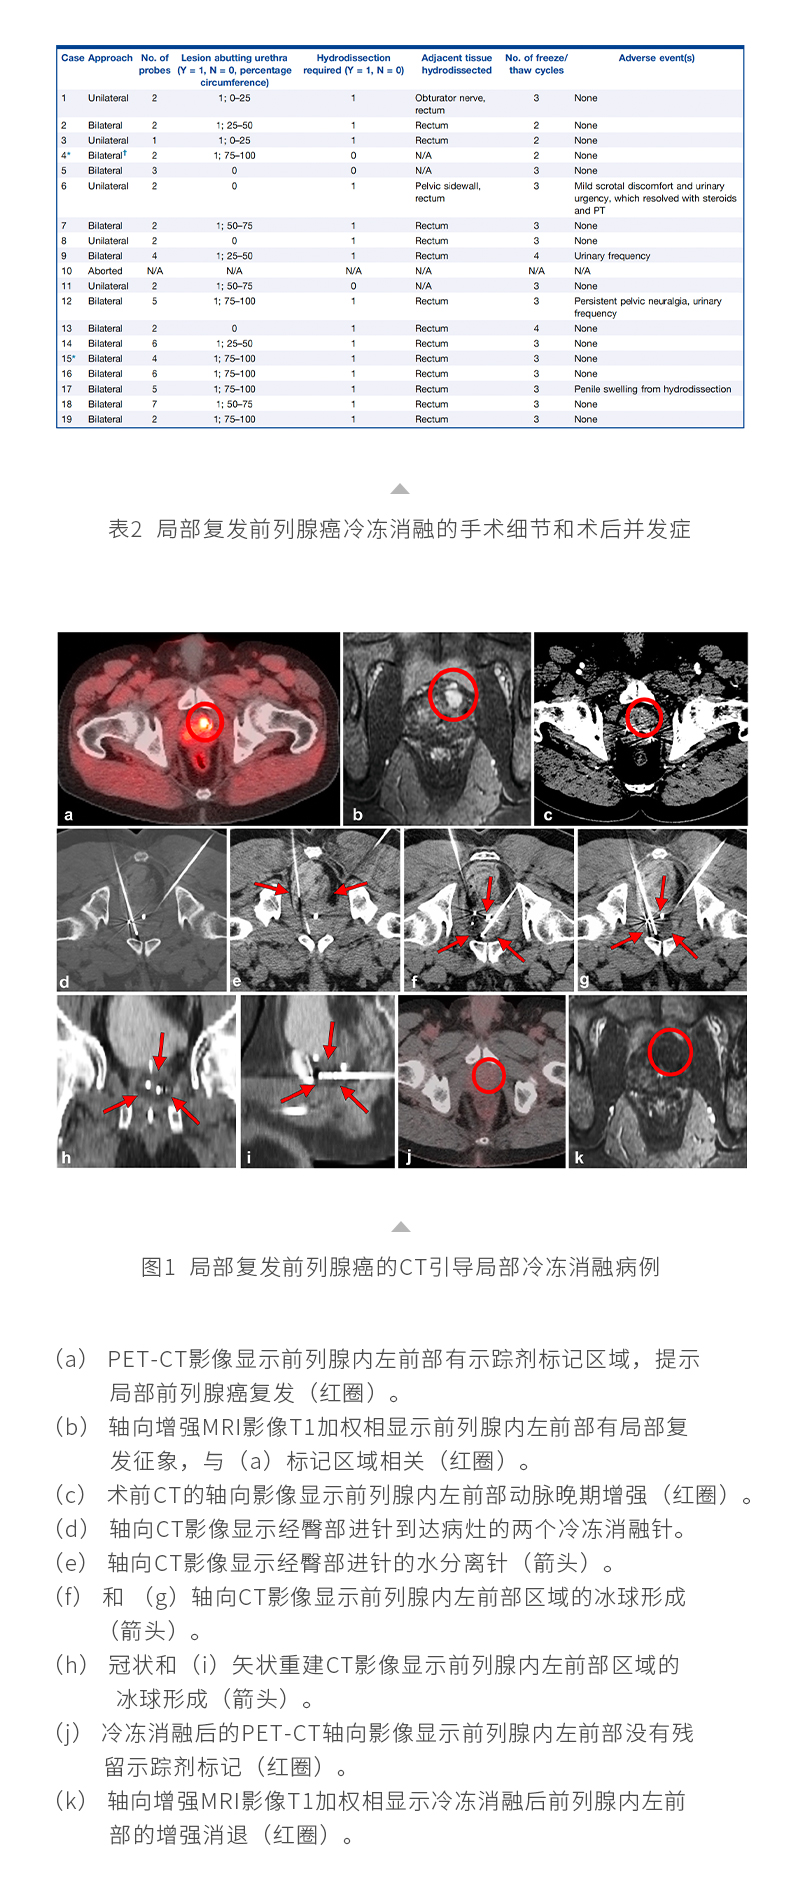

聯系我們